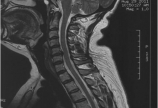

查体见:颈软无抵抗,活动度受限,左右活动各20度,C5棘突压痛(+),臂丛牵拉试验(-),胸2以下皮肤痛觉减退,四肢肌力5级,病理征未引出。辅助检查:颈部血管超声提示双侧颈动脉、椎动脉及锁骨下动脉血流未见异常;前庭功能检查提示双侧水平半椎管功能正常;头颅TCD提示右侧大脑中动脉及右侧椎动脉血流速度偏高(轻度);颅脑MRA提示双侧额叶及放射冠可见多发缺血灶,余未见明显异常;颈椎MRI提示C5-6椎间盘向后突出,硬膜囊受压迫,脊髓前缘轻度受压。颈椎过伸过屈侧位片提示颈56节段不稳。排除耳鼻喉科、神经内科疾病,2011-10-12日于颈6-7棘突间行颈硬膜外封闭试验:对比注射6ml生理盐水后,患者症状无明显改善;注射6ml 1%利多卡因后,患者2小时内未感明显头晕,无恶心、汗出等症状,视物较前清晰,飞蚊症消失,“颈性眩晕”诊断明确,无明显手术禁忌,遂继续行颈椎前路C5-6椎间盘切除术、Cage植入、钛板螺钉内固定术。手术顺利,术后患者未再次出现头晕、恶心、汗出等症状,未诉其它特殊不适;术后第二天,意外发现可正常阅读,视物重影、眼部干涩疲劳等症状消失,治疗效果满意,痊愈出院。术后随访17个月,未再出现眩晕、恶心等症状,可正常阅读,偶现飞蚊症,余无其它特殊不适。